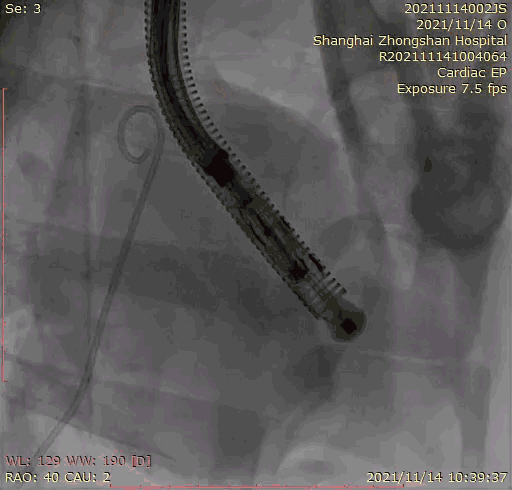

本次臨床前研究經(jīng)右側(cè)頸靜脈置入LuX-Valve Plus輸送系統(tǒng)可調(diào)彎鞘管,在DSA及超聲引導(dǎo)下將人工三尖瓣瓣膜植入到原有三尖瓣位置,利用獨特的錨定技術(shù)將人工瓣膜支架可靠固定在預(yù)定的位置。

Lux-Valve是全球第一款具有我國完全自主知識產(chǎn)權(quán)的經(jīng)導(dǎo)管介入三尖瓣置換系統(tǒng),利用前瓣夾持及室間隔錨定的復(fù)合方式進行瓣膜裝置的固定,不依賴瓣環(huán)徑向支撐力,同時采用自適應(yīng)復(fù)合裙邊材料,有效的貼合密封柔軟的三尖瓣瓣環(huán),針對于三尖瓣返流的患者有優(yōu)異的療效。Lux-Valve Plus采用全新的經(jīng)血管輸送系統(tǒng),經(jīng)頸靜脈入路創(chuàng)傷更小,可以進一步降低手術(shù)風(fēng)險。相信在后期正式臨床研究開展中,Lux-Valve Plus必定會為更多的三尖瓣反流患者帶來福音。